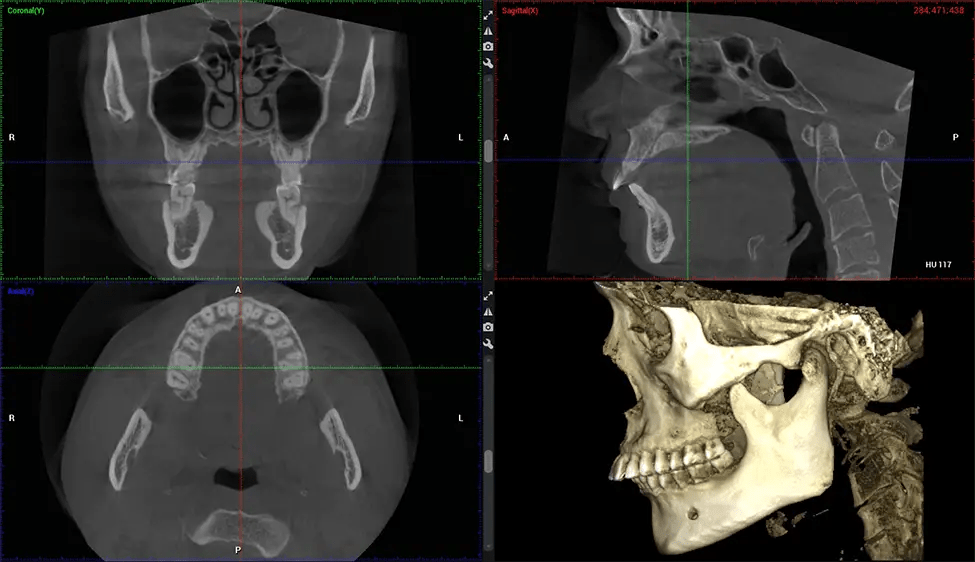

This 3D scan, called cone beam computed tomography, gives your dentist a more complete image of your oral anatomy and disease processes than a traditional X-ray. Unlike conventional X-rays, which capture a 2D image of your mouth from various angles, a 3D scan takes multiple digital X-rays for one image. It provides a complete view of your jaw, teeth, nerves, and soft tissues. This enhanced view allows dentists to detect minor issues not visible in traditional 2D scans, such as impacted wisdom teeth or bone fractures in the sinus cavity.

There are many benefits to using CBCT technology, especially compared to the traditional 2D X-ray format. One of the most significant advantages of CBCT scans is that they provide much more information than traditional X-rays. A scan lets your dentist see images from all angles of your jaw and mouth, including your sinuses, nasal cavity, cheekbones, and other surrounding areas. This added information helps your dentist craft a comprehensive treatment plan that addresses all aspects of your oral health.

Another significant benefit is that 3D imaging provides more precise images of your bone structure. These images are more detailed, providing you with a more accurate diagnosis. An accurate diagnosis means better treatment for you.

After the scanning process, the captured X-ray images are processed by the CBCT software, which applies algorithms to reconstruct a detailed 3D image of the scanned area. The software compiles these individual X-ray images and creates a digital 3D representation of the patient’s anatomy. The reconstructed 3D CBCT image can be viewed and analyzed by the dentist or radiologist. This image can be manipulated, rotated, and zoomed in or out to examine specific structures and evaluate the patient’s condition.